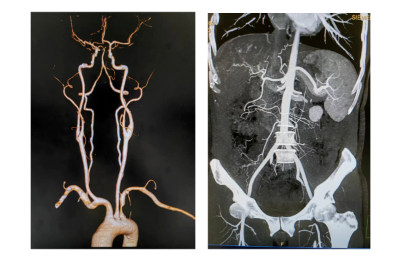

搭載Cinematic VRT三維重建技術(shù),立體還原器官、全身大血管解剖結(jié)構(gòu),對(duì)血管狹窄、斑塊性質(zhì)一目了然。 智能分析組織灌注(心肌/腦/肺),提升診斷效率與準(zhǔn)確性。

1.心腦血管疾?。?.14秒完成心臟掃描,冠脈成像不受心率限制,也同時(shí)支持心肌灌注評(píng)估。 2.腫瘤診療:雙能量技術(shù)助力良惡性鑒別、療效監(jiān)測(cè),實(shí)現(xiàn)腫瘤體積、密度的動(dòng)態(tài)追蹤。3.神經(jīng)系統(tǒng)檢查:對(duì)于腦外傷、出血、腫瘤等疾病的診斷,可提供高質(zhì)量的圖像,幫助醫(yī)生準(zhǔn)確判斷病情。雙能量活動(dòng)性腦出血分析和神經(jīng)灌注檢查,有助于評(píng)估腦卒中缺血半暗帶,為臨床治療決策提供重要參考。 4.急診與重癥:1秒全身成像快速排查多發(fā)傷、肺栓塞等急危重癥,縮短檢查時(shí)間。